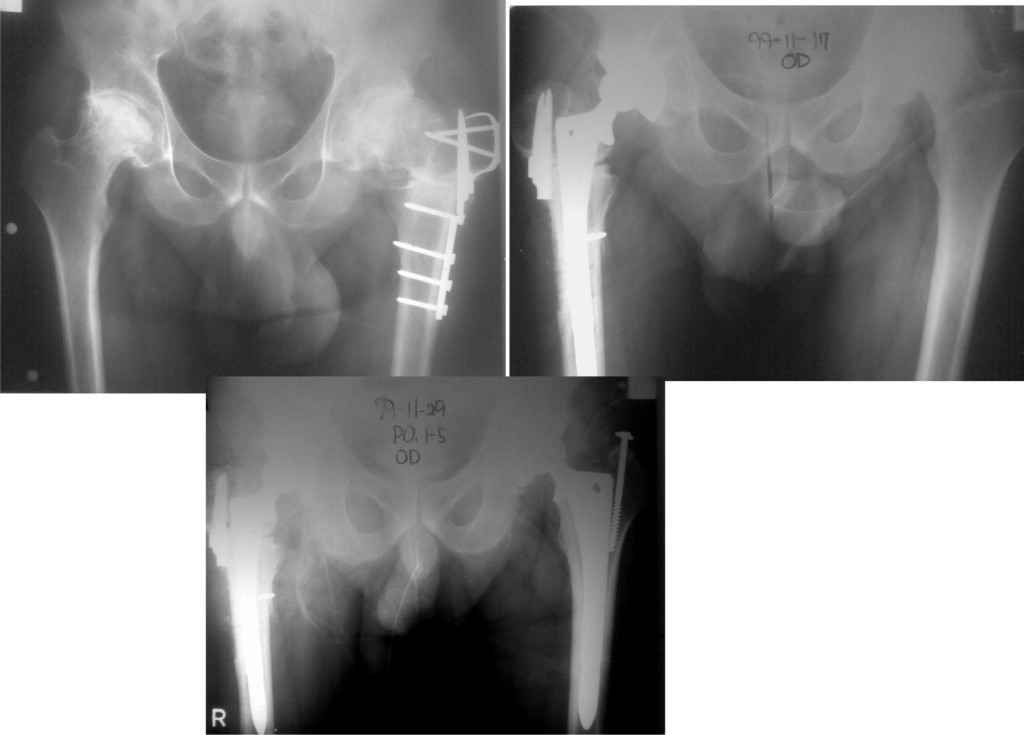

Уважаемый Станислав! Впадина недоработана, антеверзии нет, можно было на размер меньше взять тазовый компонент. Если заднего вывиха не произойдет, может все обойдется.

Какой доступ использовали? Насколько он был травматичен? Я бы дождался полного заживления раны и через пару месяцев выполнил ревизию с заменой чашки, вкладыша и, скорее всего, головки. По снимку похоже что установлена короткая головка, после переустановки чашки в правильную позицию, скорее всего, потребуется стандартная или даже плюсовая.

Доступ по Хардингу. Головка действительно S.

Чашка конечно же Variocup(Varioloc - ножка). После "погружения" чашки головку скорее всего придется менять на M или L.

Исходный сустав в приложении.

На мой взгляд, правильнее всего иметь на ревизионной операции полную линейку компонентов. Чашка тоже, скорее всего, будет больше после того как вы полноценно обработаете впадину и срубите остеофиты.

Ситуация неоднозначная, сколько специалистов, столько и мнений. Выскажу свое на основании нескольких подобных же ситуаций. Если во время установки Вы получили достаточно плотное заклинивание чашки в ВВ, плюс к этому усилили фиксацию 2-я винтами, которые так же встали плотно, то ничего страшного не происходит. Мы ведь нередко пользуемся при ревизии приемом, когда центральный дефект пластируем стружкой и вся надежда на фиксацию чашки в "риме". Если же этого пресс-фит эффекта Вы не получили и лишь "прикрутили" чашку винтами, тогда нет смысла ждать, надо исправлять ситуацию.

Уважаемый Рашид Муртузалиевич! Чашка поставлена плотно даже без винтов. Пациент достаточно активного образа жизни, есть опасения, что чашку раскачает через непродолжительное время (несколько месяцев). Про прочие проблемы, помимо чисто медицинских я уже упомянул. Для себя мы уже решили идти на ревизию, спланировали ход вмешательства, проиграли различные нештатные ситуации, подготовили соответствующий инструмен и импланты. С больным все обговорено - все риски и возможные осложнения. Достигнуто, я надеюсь взаимопонимание. Всем спасибо! Операцию запланировали на будущий вторник. Сообщу о результатах.

Если вы выполнили импакционную пластику "дна" - то волноваться особо не стоит (разве, что чашка поставлена несколько вертикально, что чревато чрезмерным износом полиэтилена), если нет, то риск асептического расшатывания очень велик, т.к. при диастазе между чашкой и костью в 2-3 мм расcчитывать на ongrowth, тем более на ingrowth не приходится. Если случился вариант 2, я бы выполнил ревизию в принятые для вашей конторы сроки (наверное после снятия швов и чистой коже), честно поговорив перед этим с пациентом.

Максим,спасибо за ответ. Между чашкой и дном - пустота. Фиксация только по краю и на винтах. Я считаю, что при нагрузке все очень быстро "развалится". Спрашиваю так настойчиво, ибо с такой ситуацией столкнулся впервые. Собственно, решение уже принято, с больным беседа проведена. На следующей неделе попытаемся взять на ревизию.

Хотелось бы увидеть рентгенограмму до имплантации. Погружение достаточное, хороший контакт с костным ложем. Центр вращения сустава сохранен. Мне кажется выбрана большая "чашка". Во всяком случае - не стоит ничего менять. Канзюба А.И.

У меня опыт по эндопротезированию совсем небольшой. Еще 5 лет тому назад у нас в городе не было протезирования. Во вложении снимки одного больного из нашего города. который оперировался в 1999 году в Южной Корее. разница по времени замены второго сустава 11 дней. Больной по настоящее время ходит без проблем, особых жалоб не предъявляет, весит он 98 кг. Может быть есть смысл подождать, по наблюдать а оперировать никогда не поздно.

К сожалению на снимках чашки просматриваются плохо. Вопрос: слева в бол. вертеле винт(на снимках после ТЭП). Это доступ с отсечением или что?

дело в том,что на снимках после замены второго сустава прослеживается ход дренажной трубки, т.е снимок контрольный сразу же после операции. Если этот доступ был с отсечением большого вертела, то не прослеживается линия остеотомии. По началу я тоже так и подумал, я считаю, что винт выполняет роль клина для стабильности ножки. Что касается качества снимков то согласен, но судя по контурам вертлужного компонента он напоминает ваш снимок.

Сегодня все-таки выполнили ревизию вертлужного компонента. Действительно, чашка держалась только по окружности, относительно легко удалилась. Так что тактику считаю правильной, ибо ловить при такой установке особо нечего было. Нестабильность в блишайшее время была бы обеспечена. Снимки после переустановки в приложении. Качество, конечно не ахти какое, это сделано на столе на плохом аппарате. Посадка проконтролирована визуально через центральное отверстие. Головку не снимали, оставили короткую. Если до ревизии длина левой ноги была +1 см, то после D=S. Теперь осталось молиться, чтобы не было осложнений. Вроде бы все прошло не травматично.